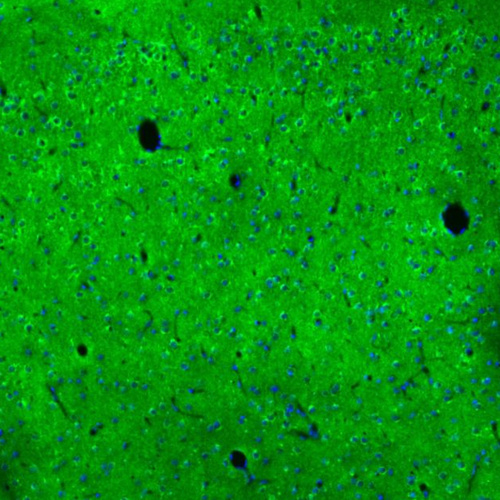

Immunohistochemical staining of human cerebral cortex shows strong granular cytoplasmic positivity in neurons and neuropil.